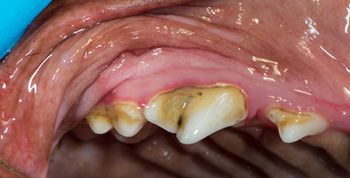

A buildup of calculus and plaque in this area can make a tooth prone to attachment loss, causing serious, painful disease if not caught early.